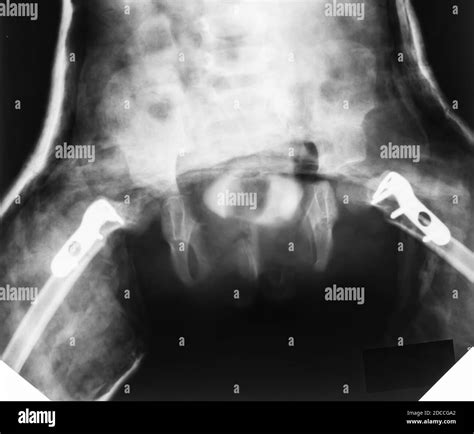

Treatment and Recovery Pathways

Recovery time for a cracked bone in hip varies based on the location of the crack and the overall health of the patient. Generally, the recovery period ranges from 6 to 12 weeks. The cornerstone of treatment is unloading the joint.

1. Immediate Immobilization and Rest

The first phase of treatment involves strict avoidance of the activities that caused the injury. You will likely need to use crutches or a walker to keep weight off the hip while the bone begins the natural healing process.